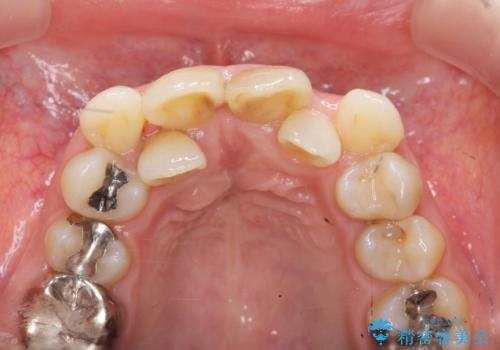

著しいがたつきによる清掃困難 歯牙抜去とセラミック治療

- 前歯の変色の改善を希望され来院されました。

X線写真より、充填剤の突き出た状態の根管治療の再治療を行い、セラミック治療を計画すると同時に、

歯ブラシがしづらく虫歯の原因となっている歯の位置の悪い右上側切歯の抜去を行います。

清掃を難しくしている歯を抜去することで虫歯の再発を防ぐような治療方針としました。